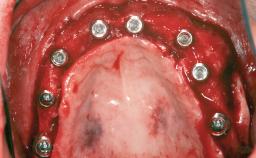

Guided Bone Regeneration (GBR) with a Particulated Autologous Graft and a ePTFE-Reinforced Membrane for Vertical Augmentation of a Single-Tooth Edentulous Space in the Esthetic Zone

A 47-year-old Caucasian woman with a single-tooth edentulous space at the site of the left maxillary canine was referred for treatment. She had undergone traumatic extraction of this impacted canine several months before referral. Her chief complaint was the dissatisfying appearance of her smile. The patient desired a stable and esthetic rehabilitation of the site. Her dental history showed no evidence of periodontal disease or bruxism. She had no systemic diseases, was not taking any medications, and did not smoke. The extraoral examination revealed a high lip line and an inadequate soft-tissue volume at the defective canine site. Large black triangles were visible between the canine and its adjacent teeth.

# of Implants | 1 |